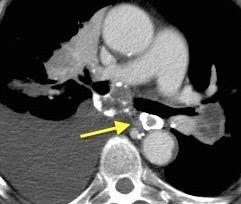

Síntomas y signos que se producen con la obstrucción total o parcial de la vena cava superior

Causas Malignas +/- 90-95%

Ca. Broncogénico (80-85%)

Linfoma No Hodgkin (15%)

Catéteres, shunts y marcapasos…23%

T. Mediastínico. Bocio

Fibrosis Idiopática

Tb, Histoplasmosis, Actinomicosis, Sarcoidosis

Carcinoma microcítico con síndrome de VCS

Grupos:

1. Obstrucción por encima de la V Ácigos. (La sangre llega al corazón a través de ella)

2. Obstrucción con participación de la V. Ácigos. (La sangre utiliza otras alternativas para llegar al corazón vía VCI).

Participación de la V. Ácigos como vía principal para llegar a la VCI.

Visible: 88%